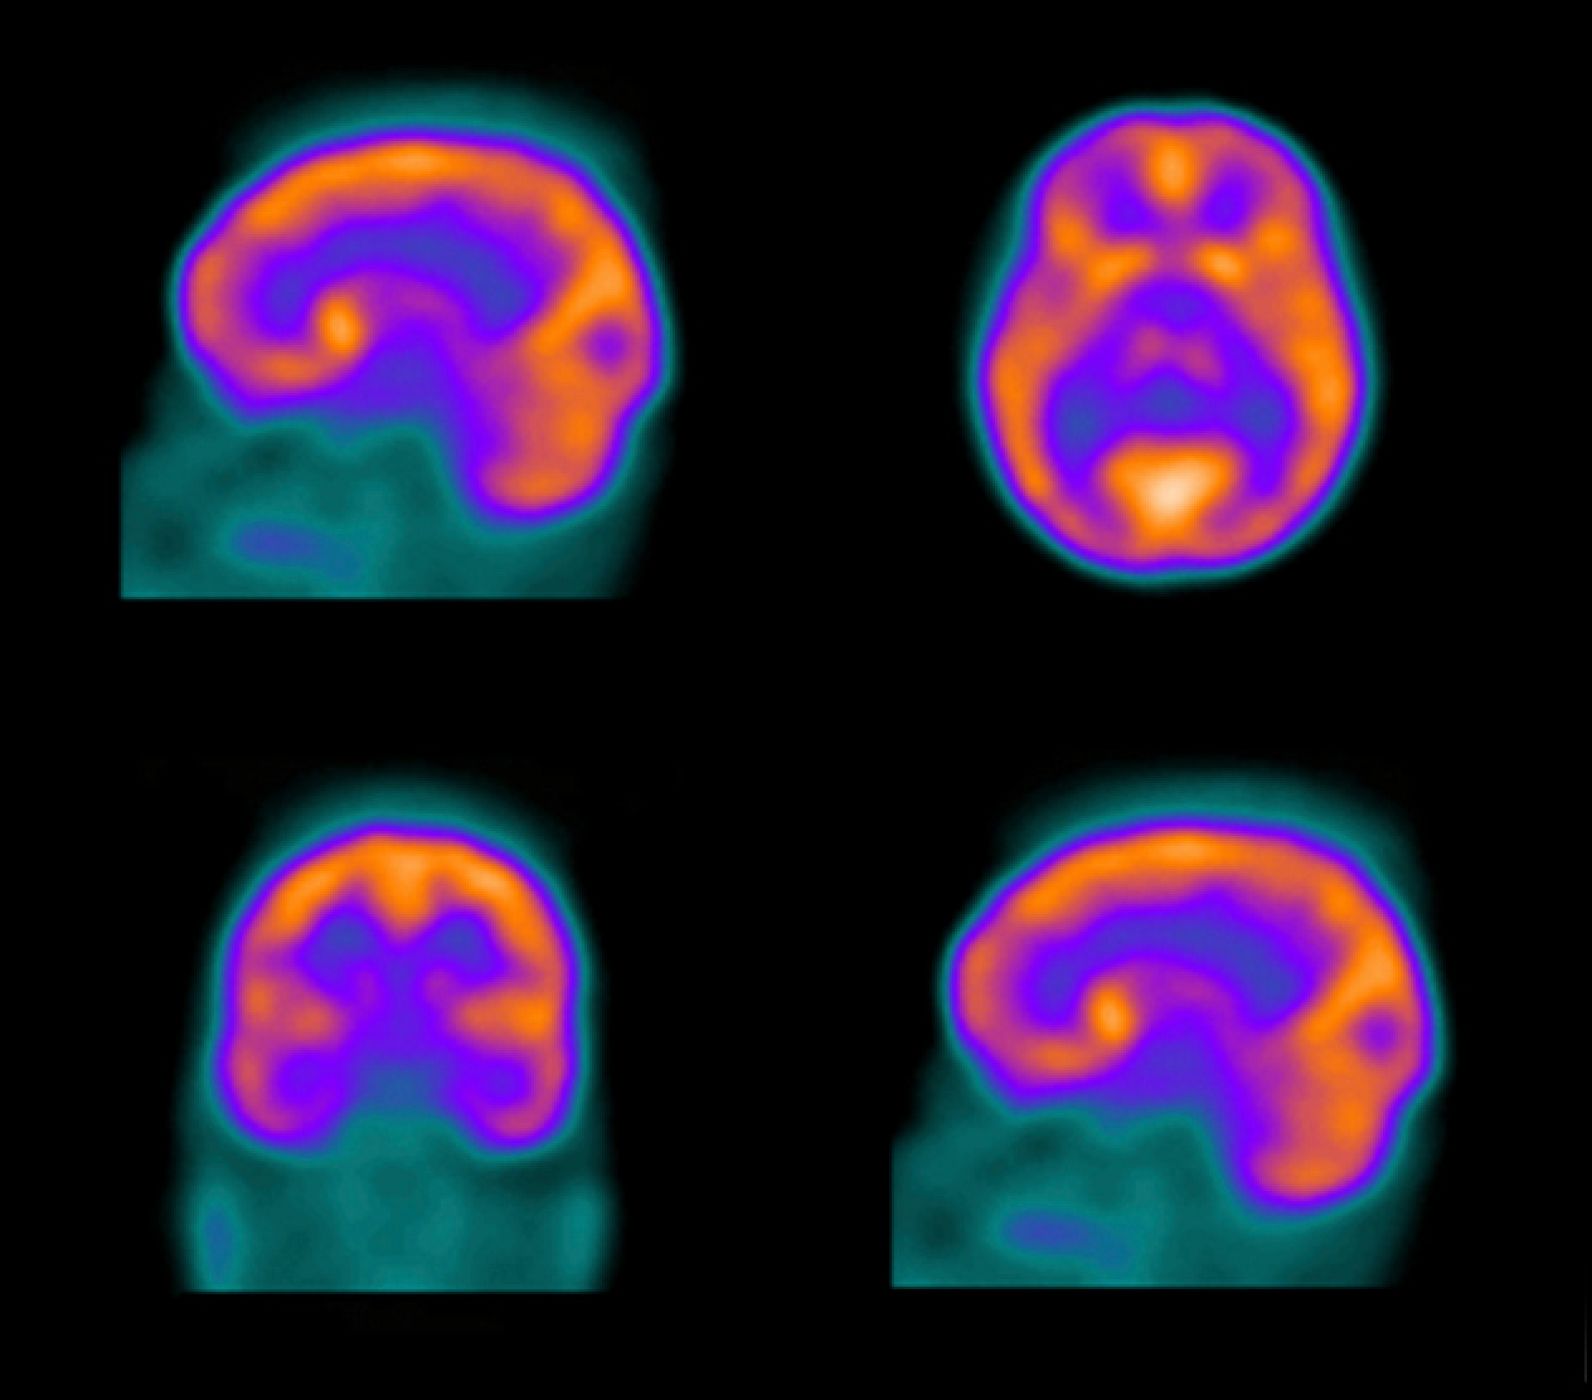

Un ictus es un trastorno brusco de la circulación cerebral que altera la función de una determinada zona del cerebro. Se produce cuando se obstruye o se rompe uno de los vasos sanguíneos que nutre a este órgano.